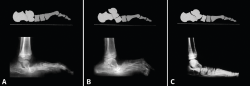

Para ello, se han estudiado radiografías de ambas entidades clínicas. Mediante la línea de Meary(3), que en un pie normal es rectilínea y atraviesa el talus, el navicular y el primer metatarsiano, se ha buscado el punto de rotura o inflexión de dicha línea en pies planos y pies cavos (Figura 1).

Figura 1. Radiografía de perfil en carga. La línea de Meary atraviesa el talus, el navicular, el cuneiforme medial y el primer metatarsiano.

Figura 2. A: la supinación del pie plano obliga al desplazamiento del primer metatarsiano a dorsal; B: en el pie cavo, por el aumento de la bóveda plantar, el primer radio se desplaza a plantar.

Siguiendo las ideas de Paparella(5), el pie plano presenta en todos los casos una anatomía patológica uniforme: existe un doble movimiento helicoidal o rotatorio en sentido inverso, el retropié está pronado y el antepié supinado, por lo que el primer radio se encuentra en flexión dorsal (Figura 2A). A ello contribuye la pérdida de potencia del peroneo largo, el cual debido al valgo de talón tiene disminuido su brazo de palanca y, por ello, menor fuerza para la flexión plantar del primer metatarsiano. El talus está desplazado hacia abajo, delante y dentro.

M. Núñez-Samper ha estudiado un grupo de pies cavos de diversas etiologías y no encuentra tampoco diferencias morfológicas del CM y de la oblicuidad de la 1.ª ATMT, con relación a un pie normal. Al aumentar la bóveda plantar, el primer metatarsiano se sitúa en flexión plantar, es decir, verticalizado (Figura 2B).